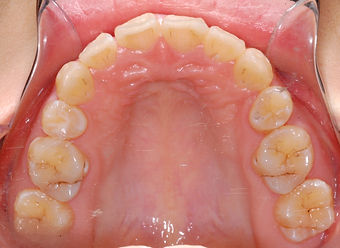

Upper

上

颚